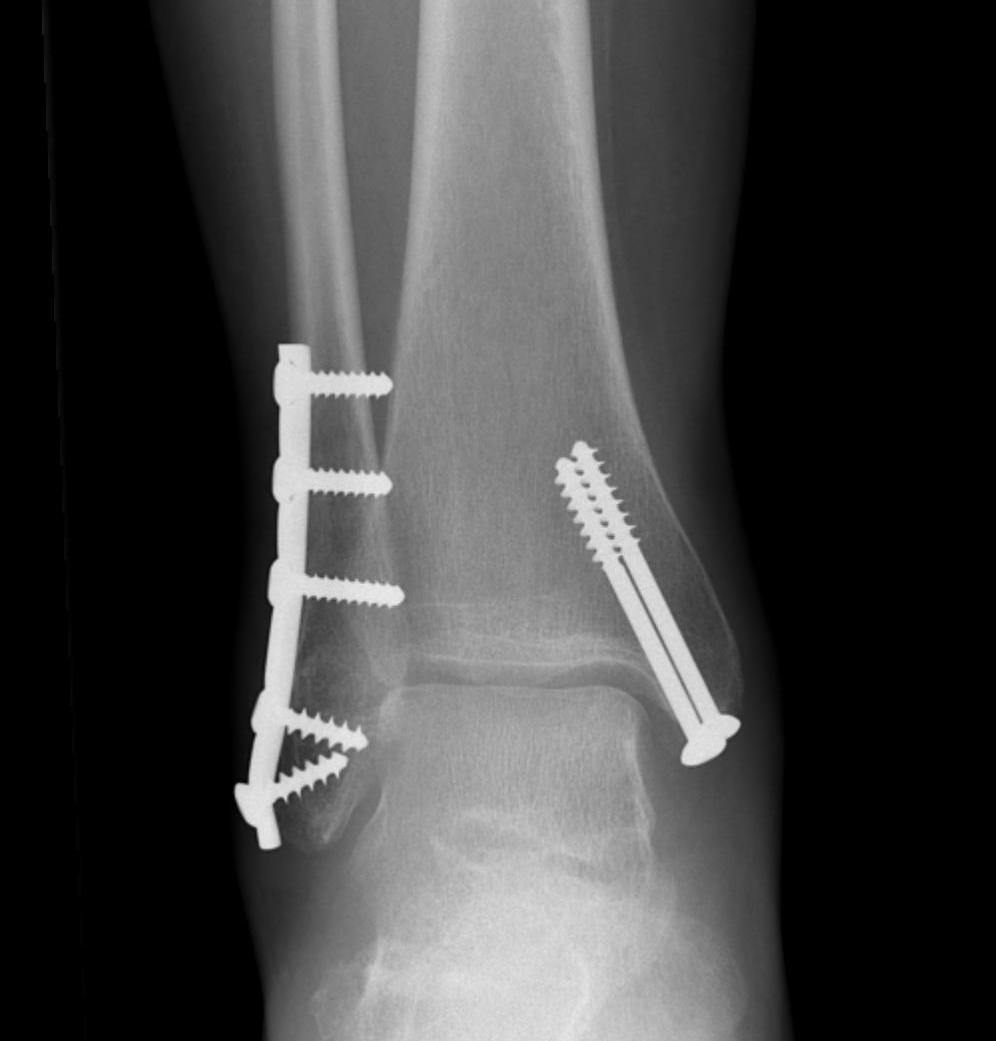

Bimalleolar Ankle Fracture ORIF [CN211213] Dr. Reaz Mahmud

BIMALLEOLAR ANKLE FRACTURE